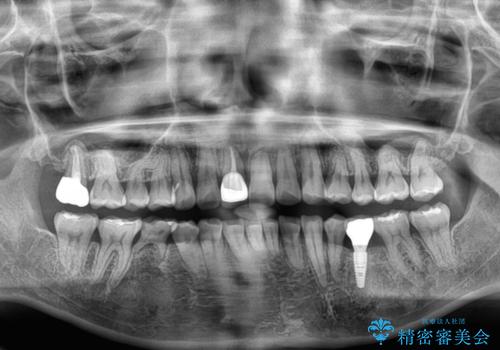

乳歯が抜け落ちた後の後続永久歯が欠損しているため、スペースが残っておりました。

口元の突出感を気にしているのであれば欠損スペースを利用して抜歯矯正を行うことも可能ですが、横顔の印象はスッキリとしている状態であったため、矯正治療でスペースを閉じきることは不可能と判断し、インプラントによる補綴治療を行うこととしました。

第二小臼歯の欠損によるが乳歯残存や欠損が多く、この乳歯は後続永久歯に比べて幅が非常に大きいため、教聖地料によるスペースクローズが難しいことが一般的です。

- 外科手術のため、術後に痛みや腫れ、違和感を伴います

- メンテナンスを怠ったり喫煙により、お口の中に大きな悪影響を及ぼすインプラント周囲炎等にかかる可能性があります

- 糖尿病、肝硬変、心臓病等の場合、インプラント治療ができない可能性があります

- 高血圧、貧血・不整脈等の場合、インプラント治療後に治癒不全を招く可能性があります